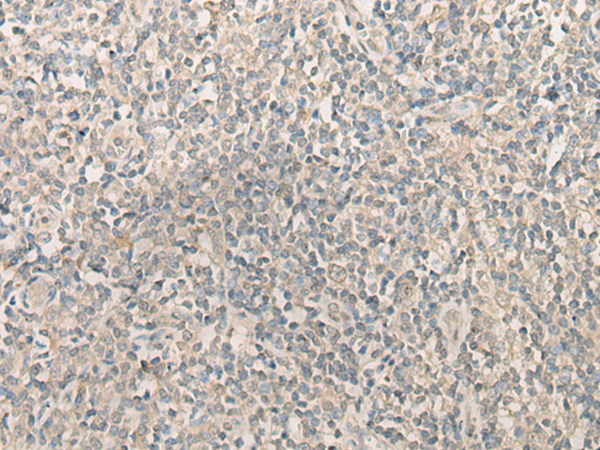

分类: 科研抗体货号: P09634别名: HEL-S-98n应用: WB,IHC反应种属: Human